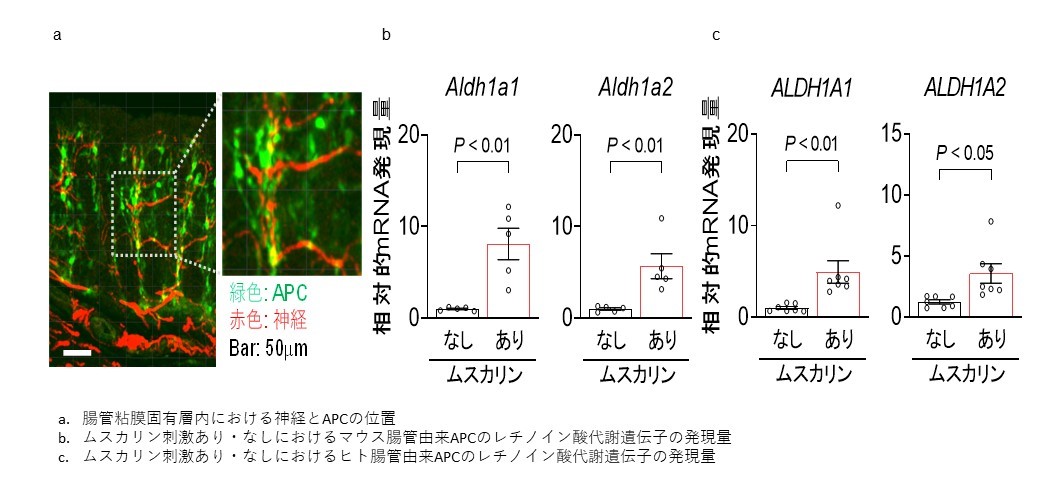

迷走神経を介した感染症・がん・炎症性腸疾患の治療に新たな光2020-06-12 慶應義塾大学医学部,日本医療研究開発機構慶應義塾大学医学部内科学教室(消化器)の金井隆典(かないたかのり)教授、寺谷俊昭特任講師、三上洋平助教を中心とするグルー...